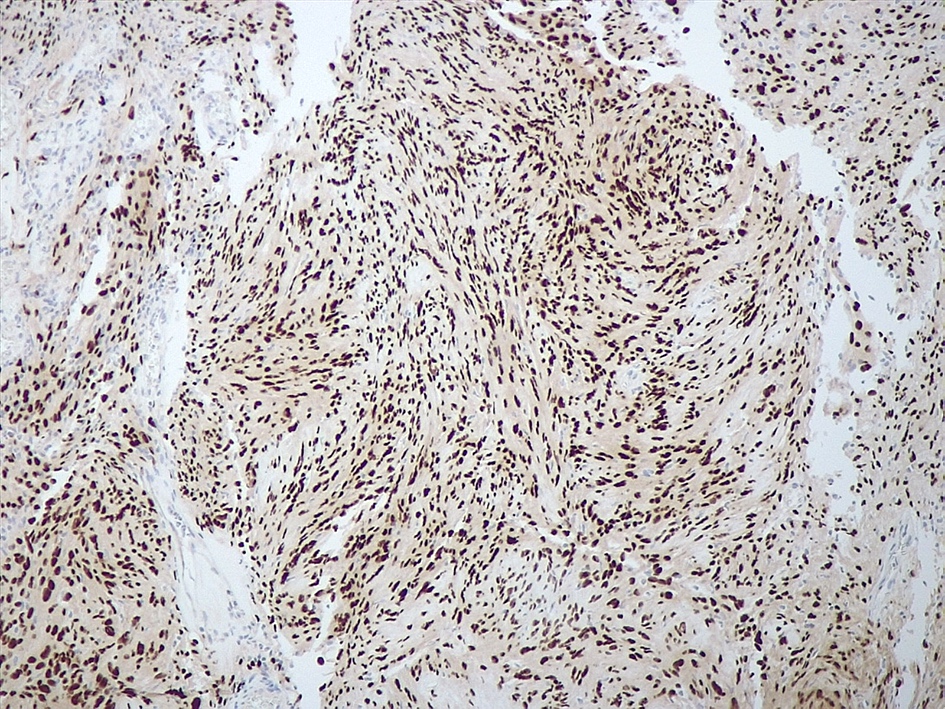

Positive stains

- Strong diffuse SOX10 (Am J Surg Pathol 2008;32:1291)

- Strong diffuse S100 (Appl Immunohistochem Mol Morphol 2012;20:445)

- Neurofilament stain demonstrates axons predominantly pushed to the periphery of the tumor